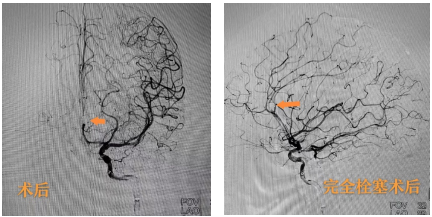

术前造影提示左侧大脑前动脉动脉瘤

术后造影提示动脉瘤完全致密栓塞,载瘤血管通畅

紧急完善术前检查后,纪文军主任医师团队为马女士急诊行全脑血管造影术。术中确诊左侧大脑前动脉瘤。纪文军主任医师紧急主持召开术前讨论,患者动脉瘤位于胼胝体旁大脑前动脉A3段,瘤颈较窄,考虑患者为年轻女性,血管通路好,适合介入栓塞治疗,决定为她行介入栓塞治疗。制定好手术方案后,由纪文军主任医师主刀,在罗有才副主任医师、李涛副主任医师、赵乐副主任医师的配合下,患者动脉瘤得以致密栓塞,载瘤动脉通畅、血流完全不受影响,患者颅内炸弹被精准拆除。为引流颅内出血,由罗有才副主任医师主刀、李涛副主任医师配合下再给患者行侧脑室穿刺引流术,手术顺利,术后患者返回神经外科二病区重症病房。